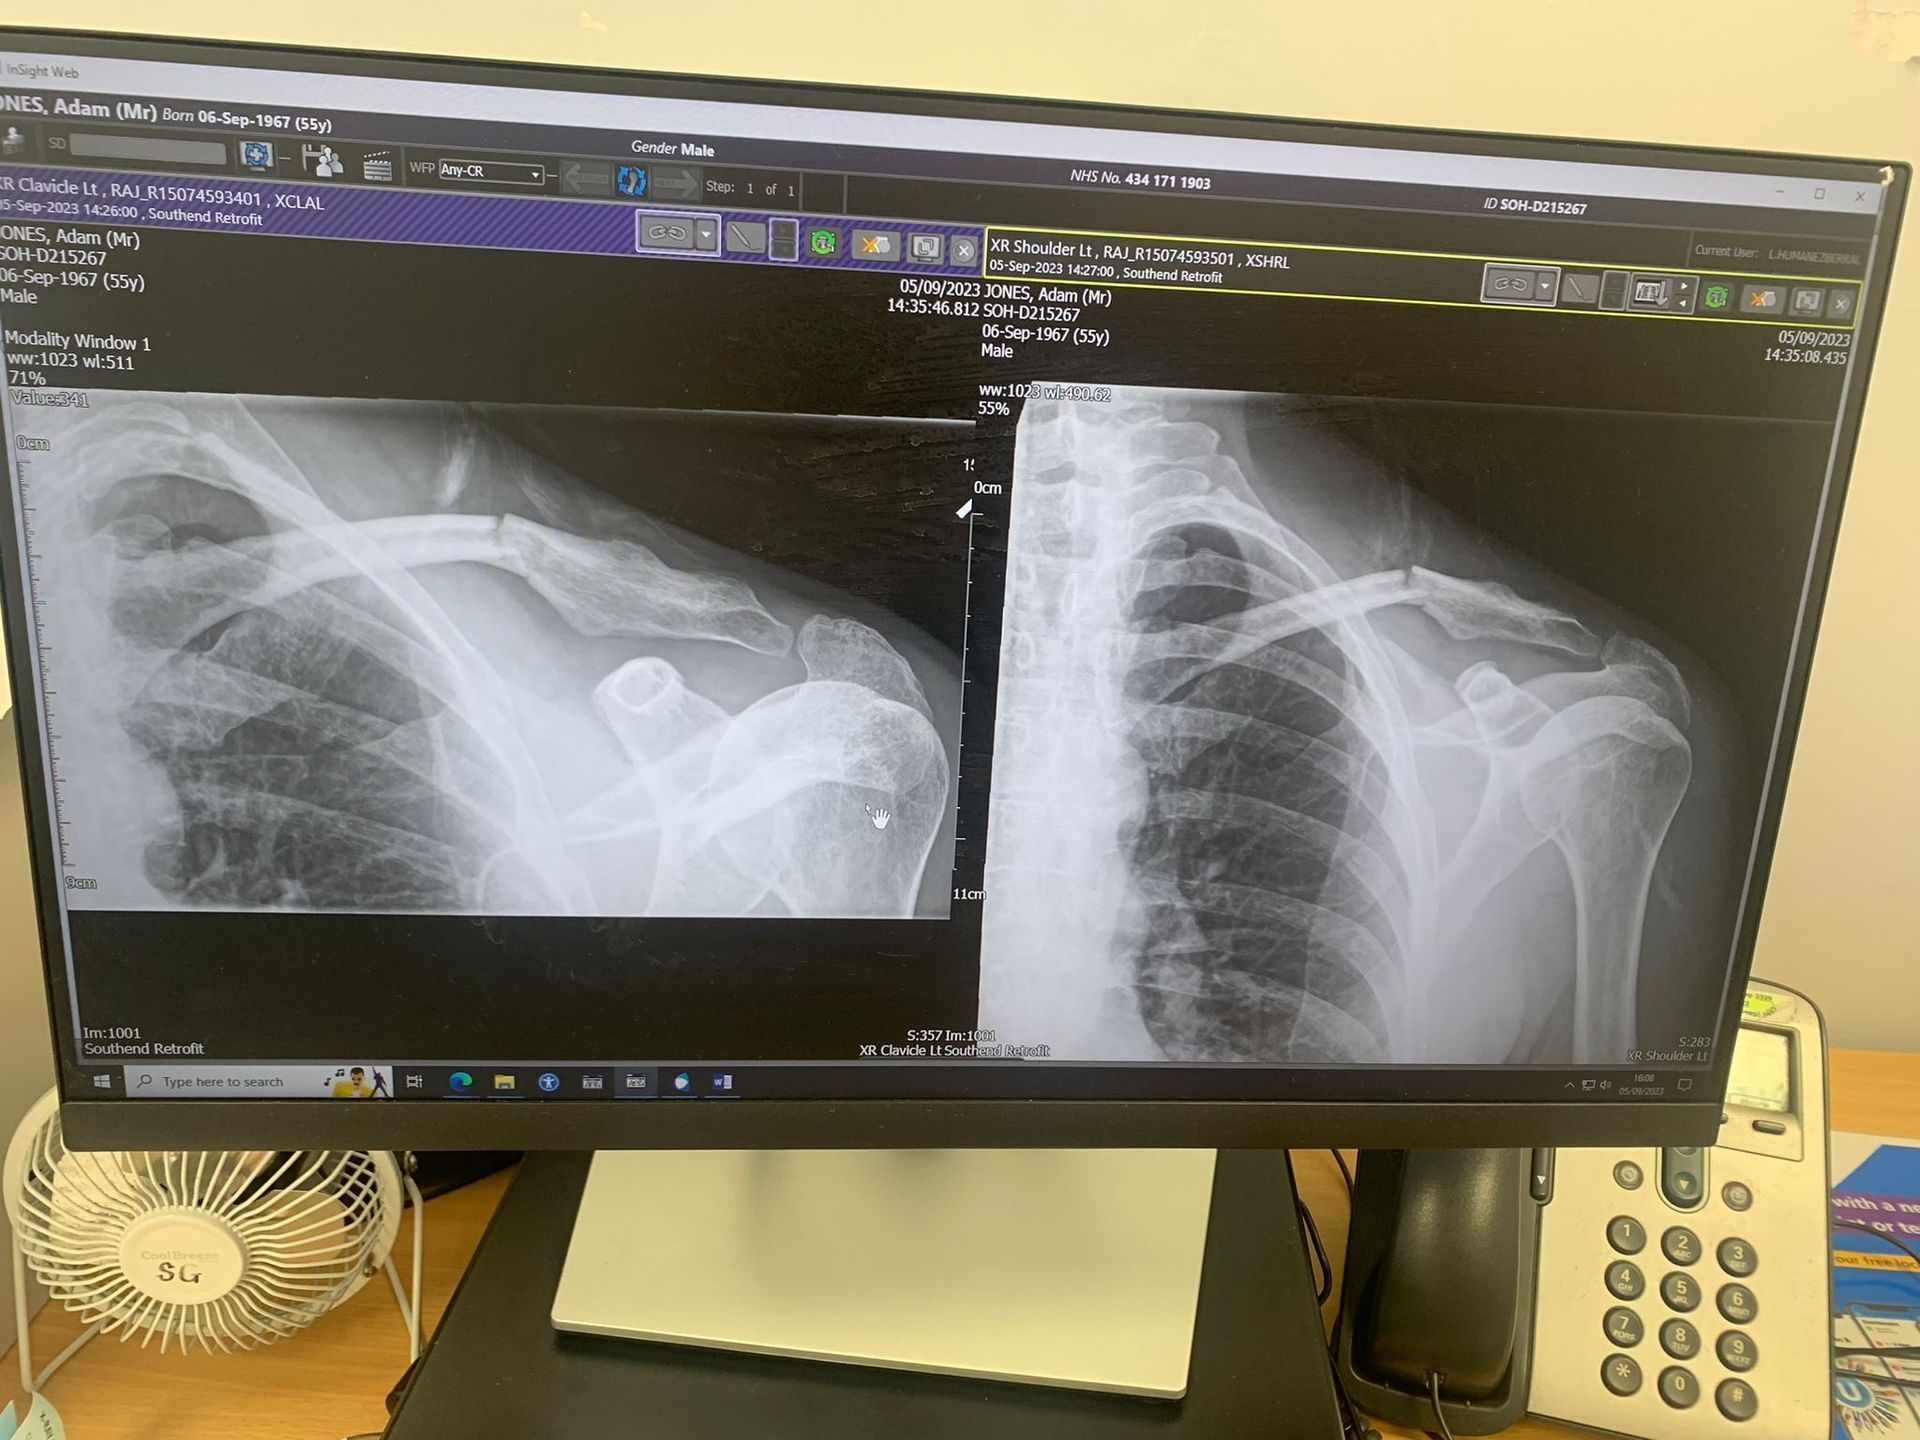

(Image credit: Adam Jones)

Looking at my x-rays, Roberts said: “You were lucky. You hadn’t displaced majorly but the previous injury, which broke the Outer Third, that’s the one that affects the ligaments that attach to your shoulder blade. It’s not a good area for healing.”

When I press him on whether a plate would have helped me, as I was so frequently advised, he says: “Part of my training was spent in the French Alps, so I saw a lot of skiers and snowboarders with collarbone injuries because they’re largely caused when you put your hand down in the process of falling. Everybody, without question, we just plated them. That was the culture. Here in the UK though, we hardly ever do this, unless the patient is a professional sports person. The reason for this is that, in the vast majority of cases, most people can be left to heal.”